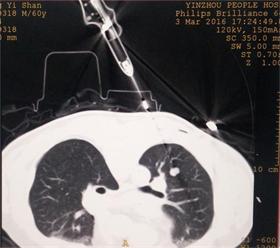

今日,我科再次为一肺部转移性肿瘤患者进行射频消融术。该患者为当地人,数年前确诊为颌面部恶性肿瘤,后经手术治愈。近日查胸部CT发现肺部有多发结节,经确诊,证实转移。在俞万钧副院长的指导下,我科顾霄,徐涛副主任医师成功对患者肺部转移性肿瘤进行定位,完整射频消融,接下去,将对患者消融的肿块进行随访,观察远期疗效。(徐涛)

图片1 射频消融前的肿瘤